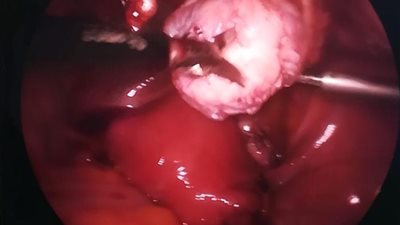

نجاح أول عملية استئصال ورم ليفي في أسيوط بفرع مستشفى جامعة الأزهر (صور)

استئصال ورم جنيني مكتمل بالبطن لطفلة 6 سنوات بأطفال بنها